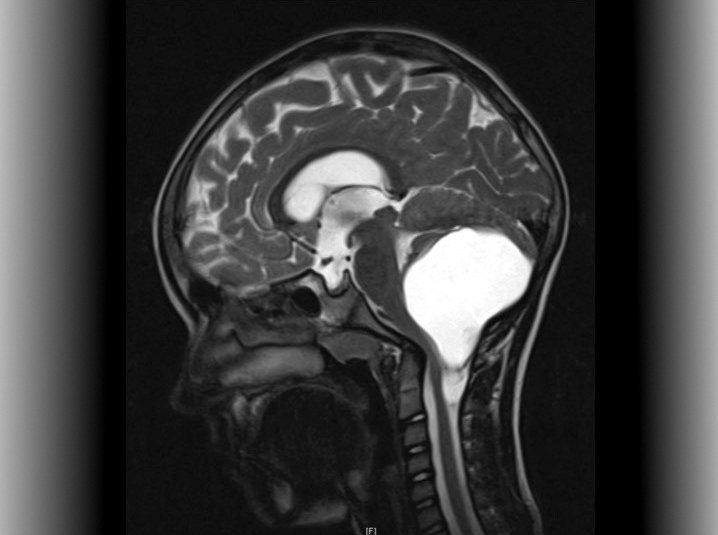

Sie sind die häufigsten Hirntumoren bei Kindern: Niedriggradige Gliome (Low Grade Glioma: LGG), eine Gruppe langsam wachsender Hirntumoren, die meist bei Kleinkindern auftreten und oftmals einen chronischen Verlauf nehmen. Die Überlebensrate zehn Jahre nach der Diagnose liegt bei 90 Prozent. Die Tumoren sind durch wechselnde Phasen von Wachstum und Stillstand gekennzeichnet. Viele Kinder benötigen im Laufe ihres Lebens daher mehrere, manchmal bis zu fünf verschiedene Therapien.

Bei einem Drittel der jungen Patienten können die Tumoren nicht durch eine Operation entfernt werden und führen zu Sehstörungen, halbseitigen Lähmungen, Hormonstörungen und Krampfanfällen. "Wir können diese Tumoren bislang nicht heilen, sondern nur durch Chemotherapien das Wachstum stoppen oder sie so lange wie möglich zurückdrängen", sagt KiTZ-Direktor Olaf Witt, der am Deutschen Krebsforschungszentrum (DKFZ) die Klinische Kooperationseinheit Pädiatrische Onkologie leitet und leitender Oberarzt am Universitätsklinikum Heidelberg (UKHD) ist. "Die Behandlung ist jedoch mit teilweise starken Nebenwirkungen und Spätfolgen für die Patienten verbunden."